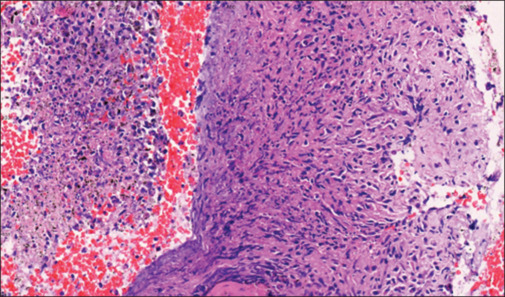

In this case report, we present a 35-year-old homosexual man with advanced HIV disease and disseminated tuberculosis (TB) who developed paradoxical TB immune reconstitution inflammatory syndrome (IRIS). Corticosteroids, vital in life-threatening IRIS, were initiated, resulting in symptom resolution but unmasking AIDS-associated Kaposi's sarcoma (KS). Diagnostic confirmation revealed disseminated KS, necessitating a comprehensive therapeutic strategy involving chemotherapy and thalidomide as a steroid-sparing agent. This case underscores the complexity of managing advanced HIV disease with IRIS, emphasizing the cautious use of corticosteroids due to the potential risk of KS unmasking. The report contributes to the limited documentation of indigenous HIV-associated KS cases in India and highlights the need for vigilant monitoring and careful therapeutic decisions in this population.